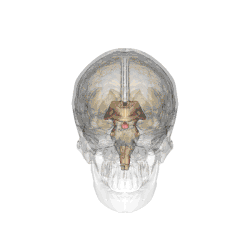

L'hypophyse se trouve dans une cavité osseuse, la fosse hypophysaire qui se situe dans l'os sphénoïde. Elle est protégée par la selle turcique. Elle est reliée à une autre partie du cerveau appelée l'hypothalamus par une tige hypophysaire (également appelée tige pituitaire). Elle produit des hormones qui gèrent une large gamme de fonctions corporelles, dont les hormones trophiques qui stimulent les autres glandes endocrines. Cette fonction lui a valu de se faire appeler par les scientifiques « glande maîtresse » du corps, mais aujourd'hui on sait que l'hypophyse est régulée par les hormones (neuro-hormones) émises par l'hypothalamus.

Chez l'être humain l'hypophyse mesure environ 10 millimètres de diamètre et pèse environ 0,5 gramme[3].

Anatomie

L'hypophyse est divisée en deux lobes : l'antéhypophyse (adénohypophyse) en avant, et la posthypophyse (neurohypophyse) en arrière. L'adénohypophyse dérive du plafond de la cavité buccale primitive (stomodeum), tandis que la neurohypophyse est une extension de l'hypothalamus, relié à celui-ci par la tige pituitaire, et contient les axones de neurones dont les corps cellulaires se trouvent dans l'hypothalamus. On peut également trouver entre l'antéhypophyse et la posthypophyse, une troisième structure, l'hypophyse intermédiaire, bien développée chez certaines espèces animales[Lesquelles ?] : chez l'humain, l'hypophyse intermédiaire (pars intermedia) est seulement visible en période fœtale et jusqu'à l'âge de dix ou vingt ans ; chez l'adulte, il subsiste quelques structures kystiques (follicules, restes de la poche de Rathke), ainsi qu'un infiltrat chromatophile basophile.